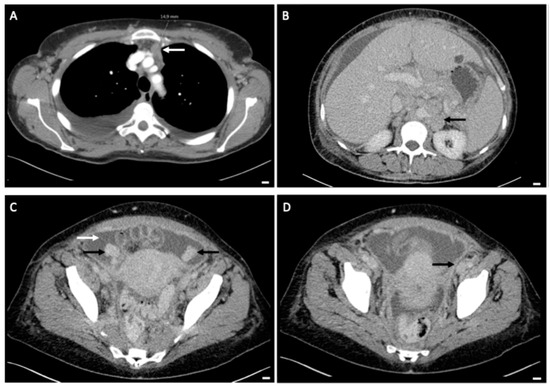

Figure 2.

Preoperative CT-imaging of thorax and abdomen. (A): Up to 15 mm pathologically enlarged retrosternal lymph node (white arrow). (B): Bulky lymph nodes paraaortal left with single lymph nodes enlarged up to 2.8 cm (black arrow). (C): Solid, up to 3 cm enlarged ovaries on both sides (black arrows), ascites (white arrow). (D): Thickened peritoneum in the small pelvis, potentially indicative of peritoneal tumor metastases (black arrow). All white bars in the bottom right-hand corner indicate 1 cm.